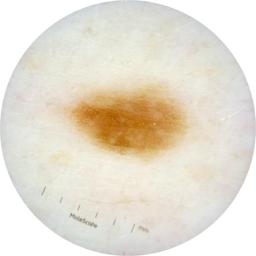

ISIC_9751750

2009 x 2009

acquisition_day 410

age_approx 50

anatom_site_1 Trunk

anatom_site_2 Posterior trunk

anatom_site_general posterior torso

diagnosis_1 Benign

diagnosis_confirm_type single image expert consensus

image_type dermoscopic